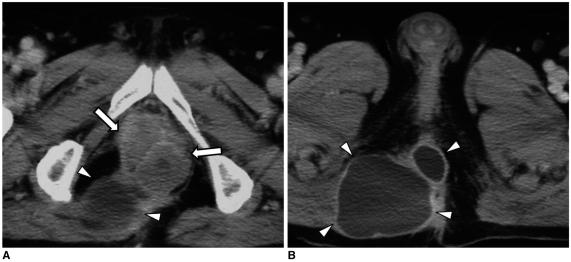

结肠癌相关结肠并发症的 CT 表现

CT findings of colonic complications associated with colon cancer.

A broad spectrum of colonic complications can occur in patients with colon cancer. Clinically, some of these complications can obscure the presence of underlying malignancies in the colon and these complications may require emergency surgical management. The complications of the colon that can be associated with colon cancer include obstruction, perforation, abscess formation, acute appendicitis, ischemic colitis and intussusception. Although the majority of these complications only rarely occur, familiarity with the various manifestations of colon cancer complications will facilitate making an accurate diagnosis and administering prompt management in these situations. The purpose of this pictorial essay is to review the CT appearance of the colonic complications associated with colon cancer.

结直肠癌患者可能会出现广泛的结肠并发症。临床上,这些并发症中的一些可能会掩盖结肠中潜在的恶性肿瘤,这些并发症可能需要紧急手术治疗。可能与结直肠癌相关的结肠并发症包括梗阻、穿孔、脓肿形成、急性阑尾炎、缺血性结肠炎和肠套叠。虽然这些并发症大多数很少见,但熟悉结直肠癌并发症的各种表现形式将有助于在这些情况下做出准确的诊断并进行及时的治疗。本文旨在通过 CT 影像回顾结直肠癌相关结肠并发症的表现。